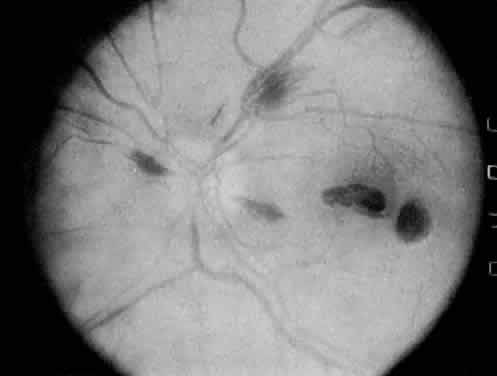

Protein S is a nonenzymatic cofactor necessary for the anticoagulant activity of activated protein C. Protein S by itself also has anticoagulant activity by forming a complex with C4b binding protein, a regulatory protein of the complement system. Protein S deficiency is inherited as an autosomal-dominant trait. Unlike protein C deficiency or antithrombin III deficiency, heterozygous protein S deficiency is not as strong a risk factor for thrombosis. Retinal artery occlusion has been described with protein S deficiency.25,29 Figure 2 shows a pregnant woman with protein S deficiency and a branch retinal artery occlusion (see Fig. 2).